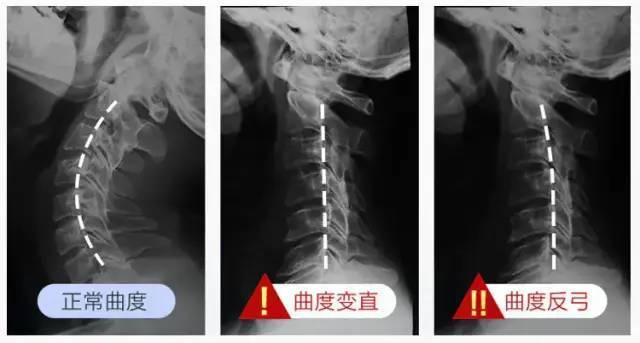

其实 , 正常人的颈椎 , 是有一定曲度的 。

可如果长期保持不健康的习惯 , 颈椎就会变直 , 严重的甚至会出现上面提到的反弓: